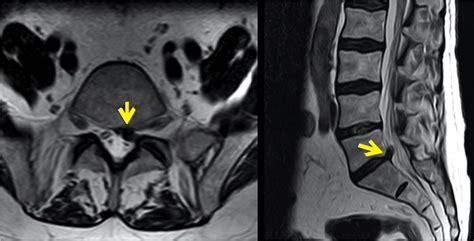

• Healthcare: Compression of medical images and data helps in efficient storage and quick retrieval, which is vital for timely diagnosis and treatment.